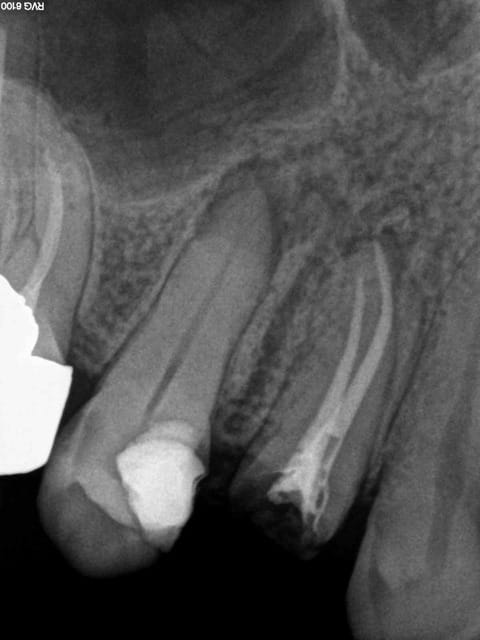

Post de depart !

Honnêtement, la dent est quand même bien niquée !

Fêlure mesiale et distale, le curetage n'est pas complet sur l'arrête restante.

Une couronne, c'est pas une connerie, patient 25-35 on tente l'onlay, patient 45-55, je couronne directement !

C'est une 6 ! 150 kg pression au cm2 !